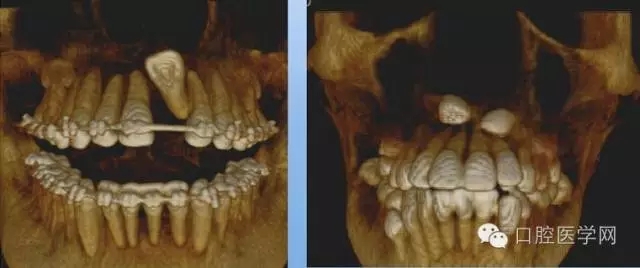

4.阻生牙

最常見于下頜第三磨牙

X線表現(xiàn):確定阻生牙的位置;確定阻生方向;牙根數(shù)目和形態(tài);阻生牙有無齲齒和根尖情況;與第二磨牙的關(guān)系;與下頜管的距離和磨牙后間隙的大小。